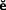

In the short term, these objectives can be accomplished with a removable occlusal device (Fig. 4-26) fabricated from clear acrylic resin that overlies the occlusal surfaces of one arch. On a more permanent basis, this can be accomplished through selective occlusal reshaping, tooth movement, the placement of restorations, or a combination of these. Definitive occlusal treatment involves accurate manipulation of the mandible, particularly in centric relation. Because the patient may resist such manipulation as a result of protective muscular reflexes, some type of deprogramming device may be needed (e.g., an occlusal device).

Occlusal devices (sometimes referred to as occlusal splints, occlusal appliances, or orthotics) are used extensively in the management of temporomandibular disorders and bruxism.54 In controlled clinical trials, they have effectively controlled myofascial pain (i.e., the patient perceives positive changes as a result of the device therapy). However, no clear hypothesis about the mechanism of action has been proved, and none of the various hypotheses (repositioning of condyle and/or the articular disk, reduction in masticatory muscle activity, modification of “harmful” oral behavior, and changes in the patient’s occlusion) has been consistently supported by scientific studies.55 Occlusal devices are particularly helpful in determining whether a proposed change in a patient’s occlusal scheme will be tolerated. The proposed scheme is created in an acrylic resin over-lay, which allows testing of the scheme through reversible means, although at a slightly increased vertical dimension. If a patient responds favorably to an occlusal device, the response to restorative treatment should be positive as well. Thus, occlusal device therapy can serve as an important diagnostic procedure before initiation of fixed prosthodontic treatment. The device can be made for either maxillary or mandibular teeth. Some clinicians express a preference for one or the other and cite advantages; however, both maxillary and mandibular devices have proved satisfactory.

There are several satisfactory methods for making an occlusal device.45 One made from heat-polymerized acrylic resin has the advantage of durability, but autopolymerizing resin used alone or in conjunction with a vacuum-formed matrix can serve equally well. Box 4-1 compares the indirect and direct techniques.

Box 4-1 Comparison of Occlusal Devices

Courtesy of Dr. J. E. Petrie.

Accurately mounted diagnostic casts are essential for this procedure. A relatively small mounting error can lead to considerable loss of time at try-in. Particular attention must be given to occlusal defects or interfering soft tissue projections on the casts, which could cause errors during mounting.

A more durable device can be made with heat-polymerized acrylic resin. The desired occlusal surface is shaped in wax on articulated diagnostic casts, or the direct device made with a vacuum-formed matrix can be used as a pattern. This is flasked and processed in a manner similar to that for a complete denture. Because of processing errors, it is important to remount the cast and make necessary adjustments before finishing and polishing are completed.

Regardless of the device chosen, success depends very much on meticulous attention to detail during the fabrication. When making a direct device, a well-adapted and stable vacuum-formed base should be used and the procedure followed exactly. For example, the clinician must be sure that the anterior guidance is properly established and that the patient’s jaw can be easily manipulated before adding resin to the posterior region. When the indirect procedure is used, the casts must articulate to an accurate centric relation record made at the correct occlusal vertical dimension. Inaccurate mounting is probably the most common cause for frustration and results in excessive adjustments at delivery.

After delivery to the patient, the occlusion must be verified and corrected as necessary. The patient is instructed to wear the device 24 hours a day, removing it only for oral hygiene, and to return at regular weekly and biweekly intervals (or sooner if a problem is anticipated) for modification. A reduction in discomfort suggests that definitive occlusal adjustment (see Chapter 6) or restorative dentistry, or both, will probably be successful. If device therapy fails to relieve the discomfort, further evaluation and diagnosis of the etiology and parameters of the chief complaint should be pursued.